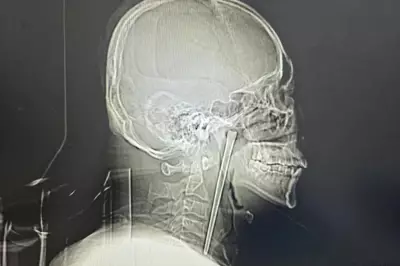

Man, 25, arrested for stabbing friend to death in Kano

Kano police confirm arrest of Mustapha Isma'il for allegedly killing his friend Halifa after a quarrel in Sheshe. The suspect has pleaded guilty. Police urge youths to avoid violence.